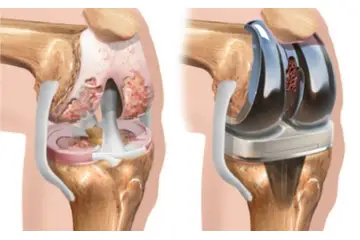

Diz kıkırdak aşınması, diz eklemindeki kıkırdak dokusunun zamanla bozulması ile ortaya çıkan bir durumdur. Yaş, aşırı kullanım, yaralanmalar ve obezite gibi faktörler bu durumu tetikler. Belirtiler arasında ağrı, sertlik ve hareket kısıtlılığı yer alır. Tedavi yöntemleri ise ilaç, fiziksel terapi ve cerrahi seçenekleri içermektedir. Bu yazıda, diz kıkırdak aşınmasının belirtileri, nedenleri ve tedavi yöntemleri detaylı bir şekilde ele alınmaktadır.

Diz Kıkırdak Aşınması Belirtileri ve Tedavisi Diz kıkırdak aşınması, diz ekleminde bulunan kıkırdak dokusunun zamanla bozulması ve incelmesi durumudur. Bu durum, genellikle yaşlanma, aşırı kullanım, yaralanmalar ve obezite gibi faktörlerden kaynaklanmaktadır. Kıkırdak, eklemler arasında amortisör görevi görerek, kemiklerin birbirine sürtünmesini önler. Kıkırdak aşınması, dizdeki ağrı, sertlik, şişlik ve hareket kısıtlılığı gibi belirtilerle kendini gösterir. Bu makalede, diz kıkırdak aşınmasının belirtileri, nedenleri ve tedavi yöntemleri üzerinde durulacaktır. 1. Diz Kıkırdak Aşınmasının Belirtileri Diz kıkırdak aşınmasının belirtileri, hastalığın ilerlemesine bağlı olarak değişiklik gösterebilir. Genel olarak görülen belirtiler şunlardır:

4. Tedavi Yöntemleri Diz kıkırdak aşınması tedavisi, hastanın durumuna ve aşınmanın derecesine bağlı olarak değişmektedir. Tedavi yöntemleri şunları içermektedir: